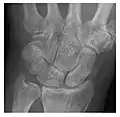

- a

- b

- c

Figure 3: A 26-year-old man presenting with wrist pain after being assaulted. (a) Initial anteroposterior radiograph shows a subtle linear lucency within the scaphoid extending to the scaphocapitate articular surface that was overlooked (arrow). (b) Initial "scaphoid" view was negative. (c) Followup anteroposterior radiographs, 12 days later, shows obvious scaphoid fracture (arrows).[1]